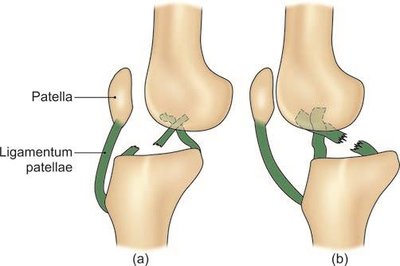

Ligamentum patellae: Connects the patella to the tibia.

Anterior: Quadriceps femoris, patella, ligamentum patellae.